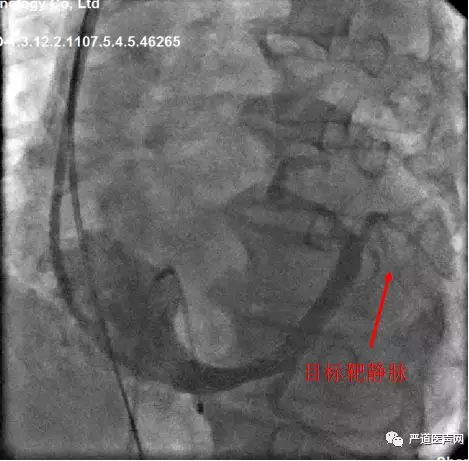

● LAO发现走形左室侧的靶静脉有三根,RAO发现侧静脉两根,但是与主干分支处有迂回夹角

● 将心房和右室电极植入后,调整左室电极电极位置,目标靶静脉为偏下的侧静脉。但是很明显发现夹角锐利,左室四级电极无法通过,故选择130度夹角的鞘中鞘做支撑